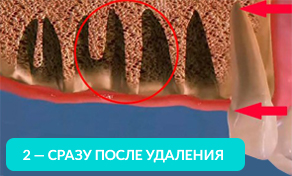

Как говорилось ранее, из-за отсутствия зубов, начинает происходить убыль костной ткани и её толщины может не хватить, чтобы установить имплант.

Отсутствие хотя бы одного зуба приводит к лавинообразной потери оставшихся.

Оставшиеся зубы начинают заполнять пустоты и смещаться.

На рисунке видно, какие щели между зубов образуются уже через год, после удаления.

Оставшиеся зубы смещаются в сторону и вытягиваются из десны. Зубам необходимо иметь опору (особенно при жевании). Если такой опоры нет, то они начинают ее искать и выдвигаться из десны.

Через год изменения уже будут видны невооруженным глазом. Выдвинутый зуб будет мешать при протезировании противоположного. Придется подпиливать выдвинувшийся зуб или возвращать его на место с помощью ортоимплантов.

Смещаясь, зуб начинает притираться к соседним, повреждая эмаль — возникает кариес:

На 4-ом рисунке видно, что костная ткань стала значительно тоньше, теперь в это место уже невозможно установить импланты (потребуется операция по наращиванию костной ткани).

Обратите внимание, насколько тоньше стала кость на рисунке 4, как постепенно обнажается корень оставшегося зуба.